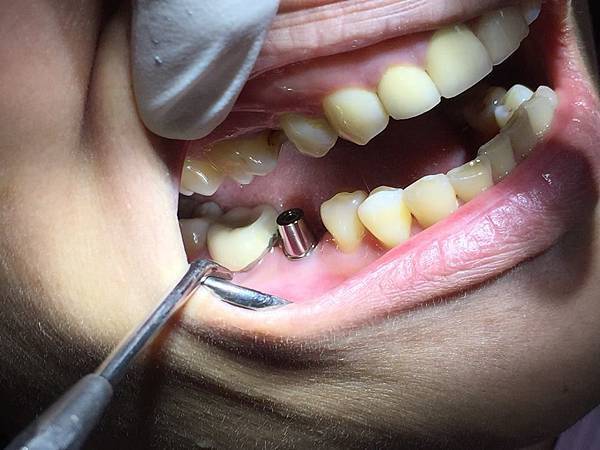

這個階段是醫師植入植體後縫合傷口的照片,手術期間雖然有局部麻醉,但超怕痛的我,還是感受的到醫師從頭到尾都非常的小心翼翼,不要看流血那麼多很可怕,其實手術過程是不太會感覺到疼痛的!術後也只要好好保養,不要讓傷口發炎,加上醫師指示按時冰敷也會好很多喔

放入植體的三個月後放置牙肉成形器,植體上面有凸起的地方就是牙肉成形器,為了讓牙肉照著圓形的成形器長出漂亮的牙肉